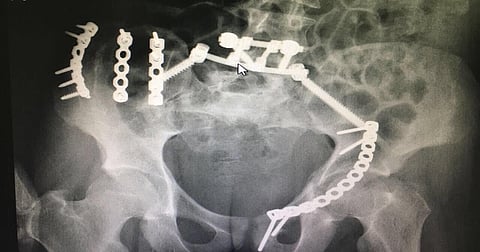

وأضاف أنه تم عمل إرجاع وتثبيت داخلي لجميع الكسور والخلع من الأمام والخلف، وذلك خلال عملية استغرقت قرابه ثماني ساعات وتكللت بالنجاح.

وأشار إلى أن العملية معقدة، وأُجريت بعد أخذ كامل الفحوصات الطبية، وذلك على يده ومعه فريق طبي سعودي يتكون من الدكتور أنور الربيعة استشاري العمود الفقري بمستشفى الملك فيصل التخصصي والدكتور عبدالله الزهراني استشاري الكسور بمستشفى الحرس الوطني، بالإضافة إلى الدكتور ماهر الزهراني استشاري الكسور بمدينة الأمير سلطان الطبية.